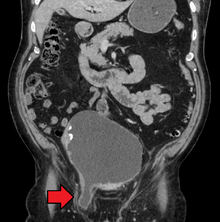

After the diagnosis is suspected, it is often confirmed by imaging. When assessed by ultrasound or cross sectional imaging with CT or MRI, the major differential in diagnosing indirect inguinal hernias is differentiation from spermatic cord lipomas, as both can contain only fat and extend along the inguinal canal into the scrotum.[9]

On axial CT, lipomas originate posterolateral to the cord, and are located inside the cremaster muscle, while inguinal hernias lie anteromedial to the cord and are not intramuscular. Large lipomas may appear nearly indistinguishable as the fat engulfs anatomic boundaries, but they do not change position with coughing or straining.[9]